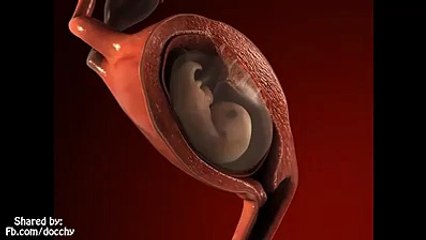

FECUNDACION Y DESARROLLO EMBRIONARIO HASTA EL 1ER TRIMESTRE